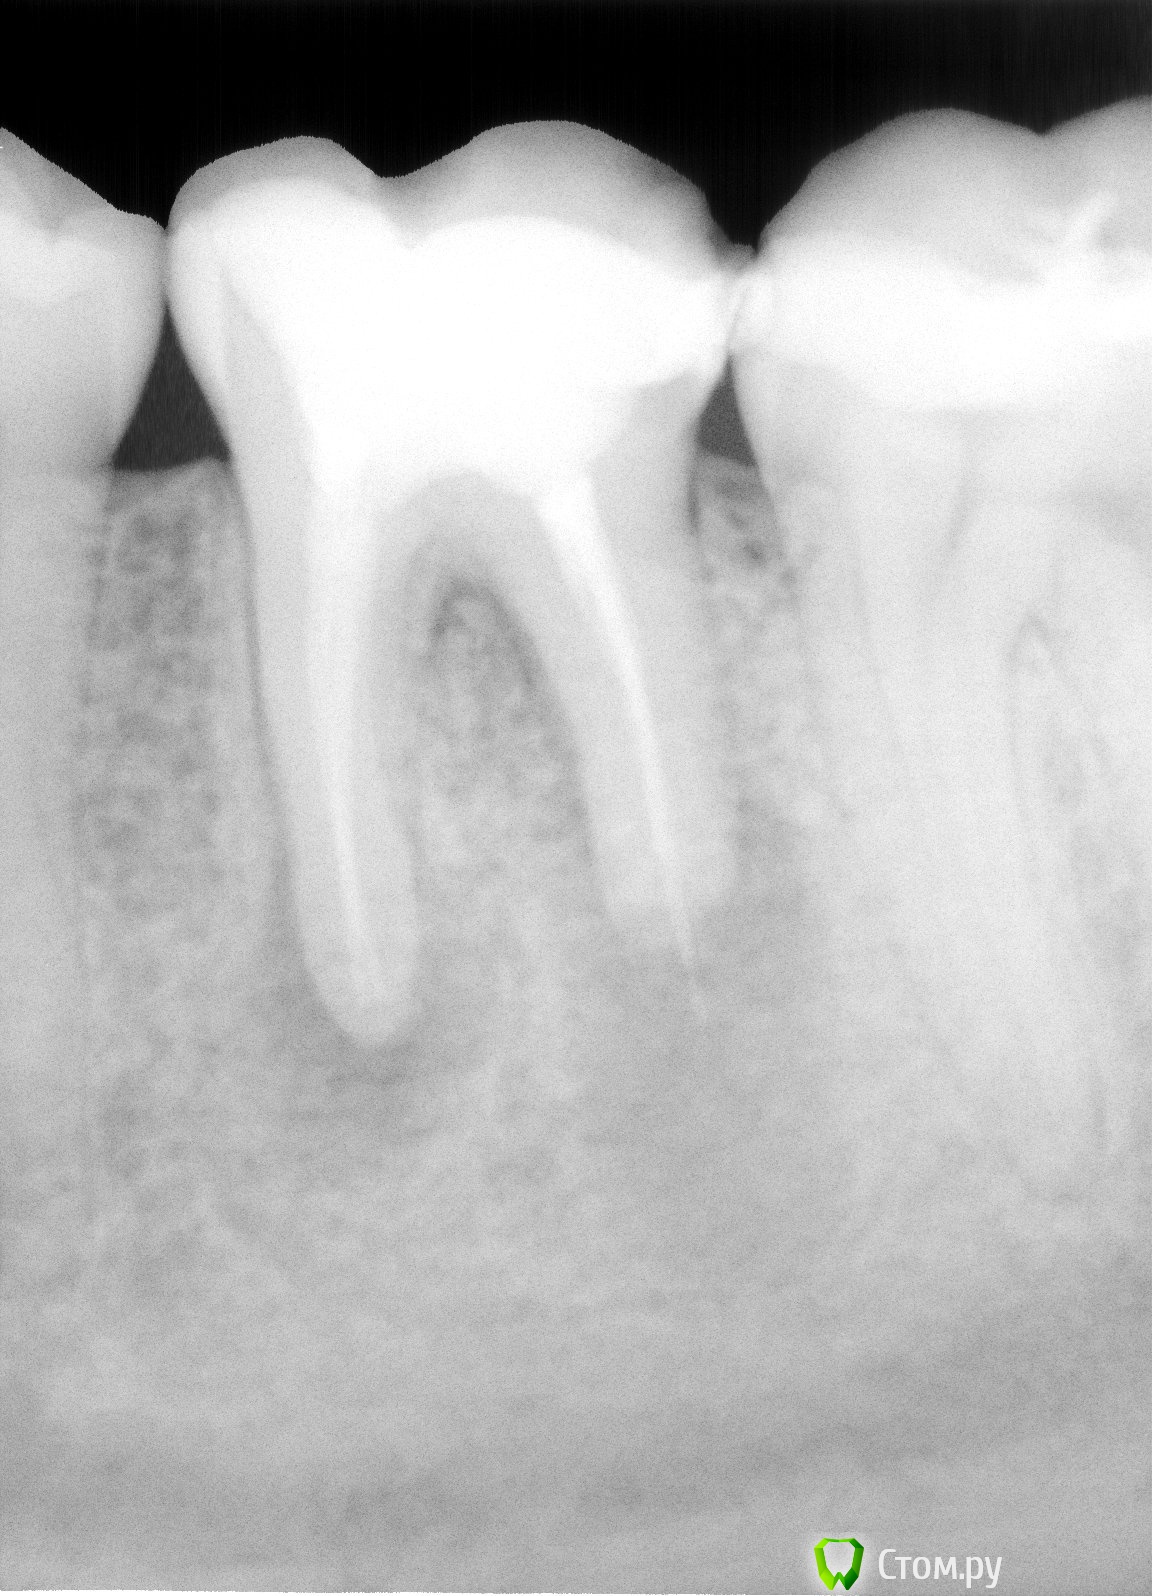

vovka2 Опубликовано 16 января, 2014 Поделиться Опубликовано 16 января, 2014 (изменено) Добрый день хотел задать вопрос по поводу кисты зуба. Около 5 лет назад разболелся 6 нижний левый зуб пошел к стоматологу зуб поставлена была временная пломба, затем на второй приход зуб депульпировали и поставили пломбу. Недавно этот зуб немножко надломился с краешку незначительно. Перед тем как исправить дефект на зубе врач на всякий случай сделали рентген и сказал что там киста и надо удалять зуб, что лечение в данном случае не принесет результатов.Хотелось бы узнать ваше мнение доктора насколько срочная ситуация. Тк зуб абсолютно не беспокоит. Заранее благодарю.. Снимки прилагаются.. Изменено 16 января, 2014 пользователем vovka2 Ссылка на комментарий

DmitrySH Опубликовано 16 января, 2014 Поделиться Опубликовано 16 января, 2014 Я предложил попробовать лечение. Ничего очень страшного тут не вижу. Ссылка на комментарий

DmitrySH Опубликовано 17 января, 2014 Поделиться Опубликовано 17 января, 2014 опять мнения разделились )) Так это же хорошо. По теме считаю, что вопрос можно решить и хирургически и терапевтически. 1 Ссылка на комментарий